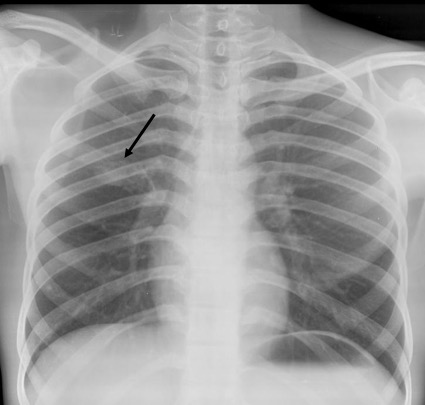

Frontal radiograph of the right hemithorax shows a relatively well defined approximately 2 cm sized oval soft tissue density nodule in the right middle zone. No calcification or cavitation. There is no other nodule. No effusion. No suspicious bone lesion.

Case courtesy of Dr Ayush Goel, <a href=”https://radiopaedia.org/”>Radiopaedia.org</a>. From the case <a href=”https://radiopaedia.org/cases/29150″>rID: 29150</a>

Note that the description of the nodule should always include its shape (round/oval, spiculated, lobulated etc), and presence or absence of cavitation and calcification. Unless the nodule demonstrates certain findings consistent with a benign etiology, it should be labelled as indeterminate and should be further evaluated with a CT/biopsy.